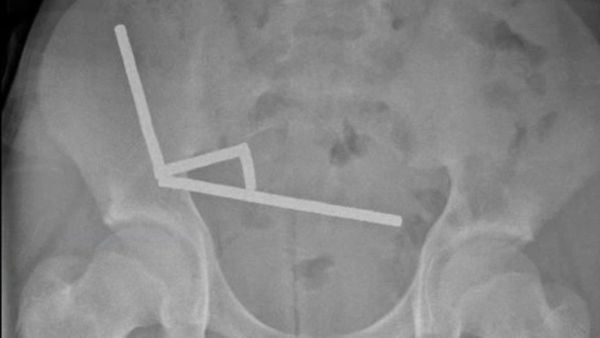

Рентгеновата снимка показва четири линейни вериги в отделни части на червата. Веднага подготвят момчето за операция. По време на нея става ясно, че погълнатите магнити не са 100, а почти 200.